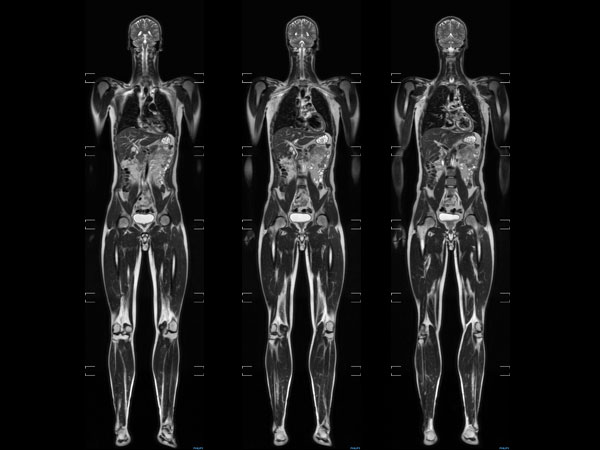

Total Body Imaging

Whole Body imaging